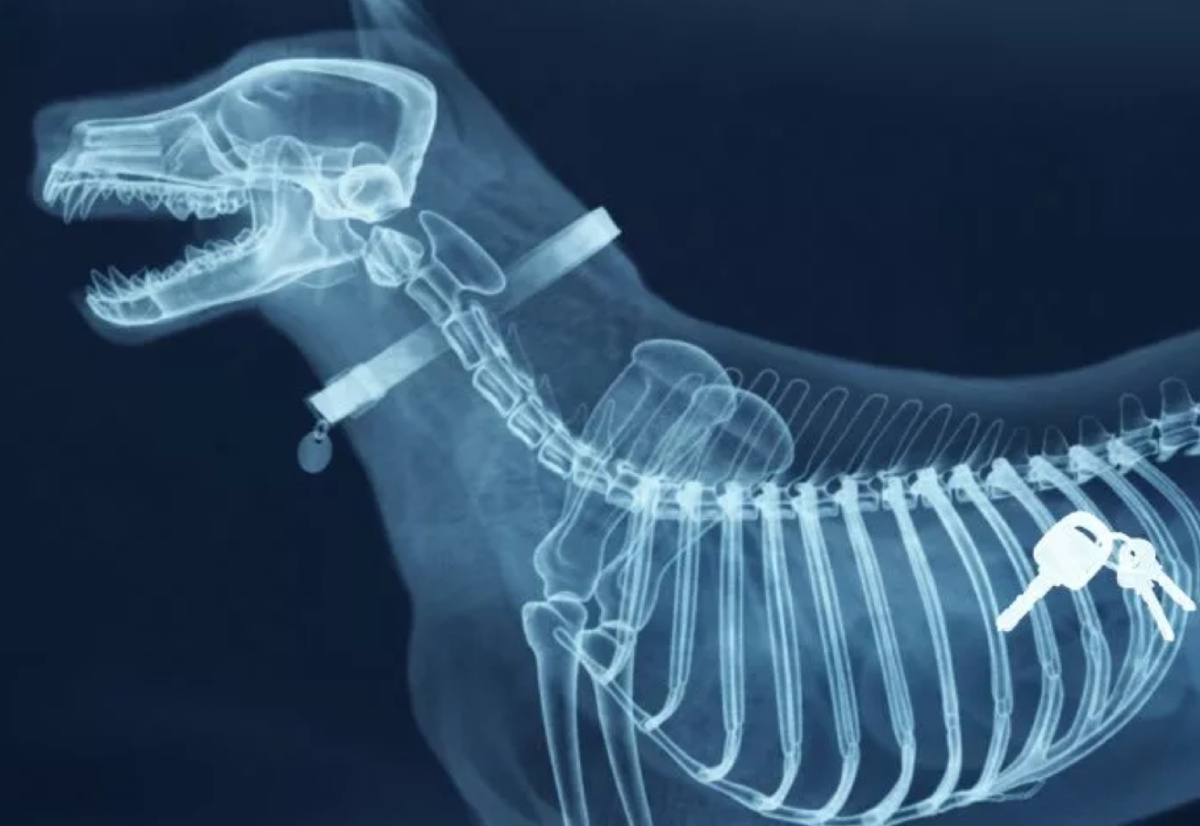

• Мелкие предметы - Монеты, ключи, кнопки, швейные принадлежности.

• Рентген-исследование.